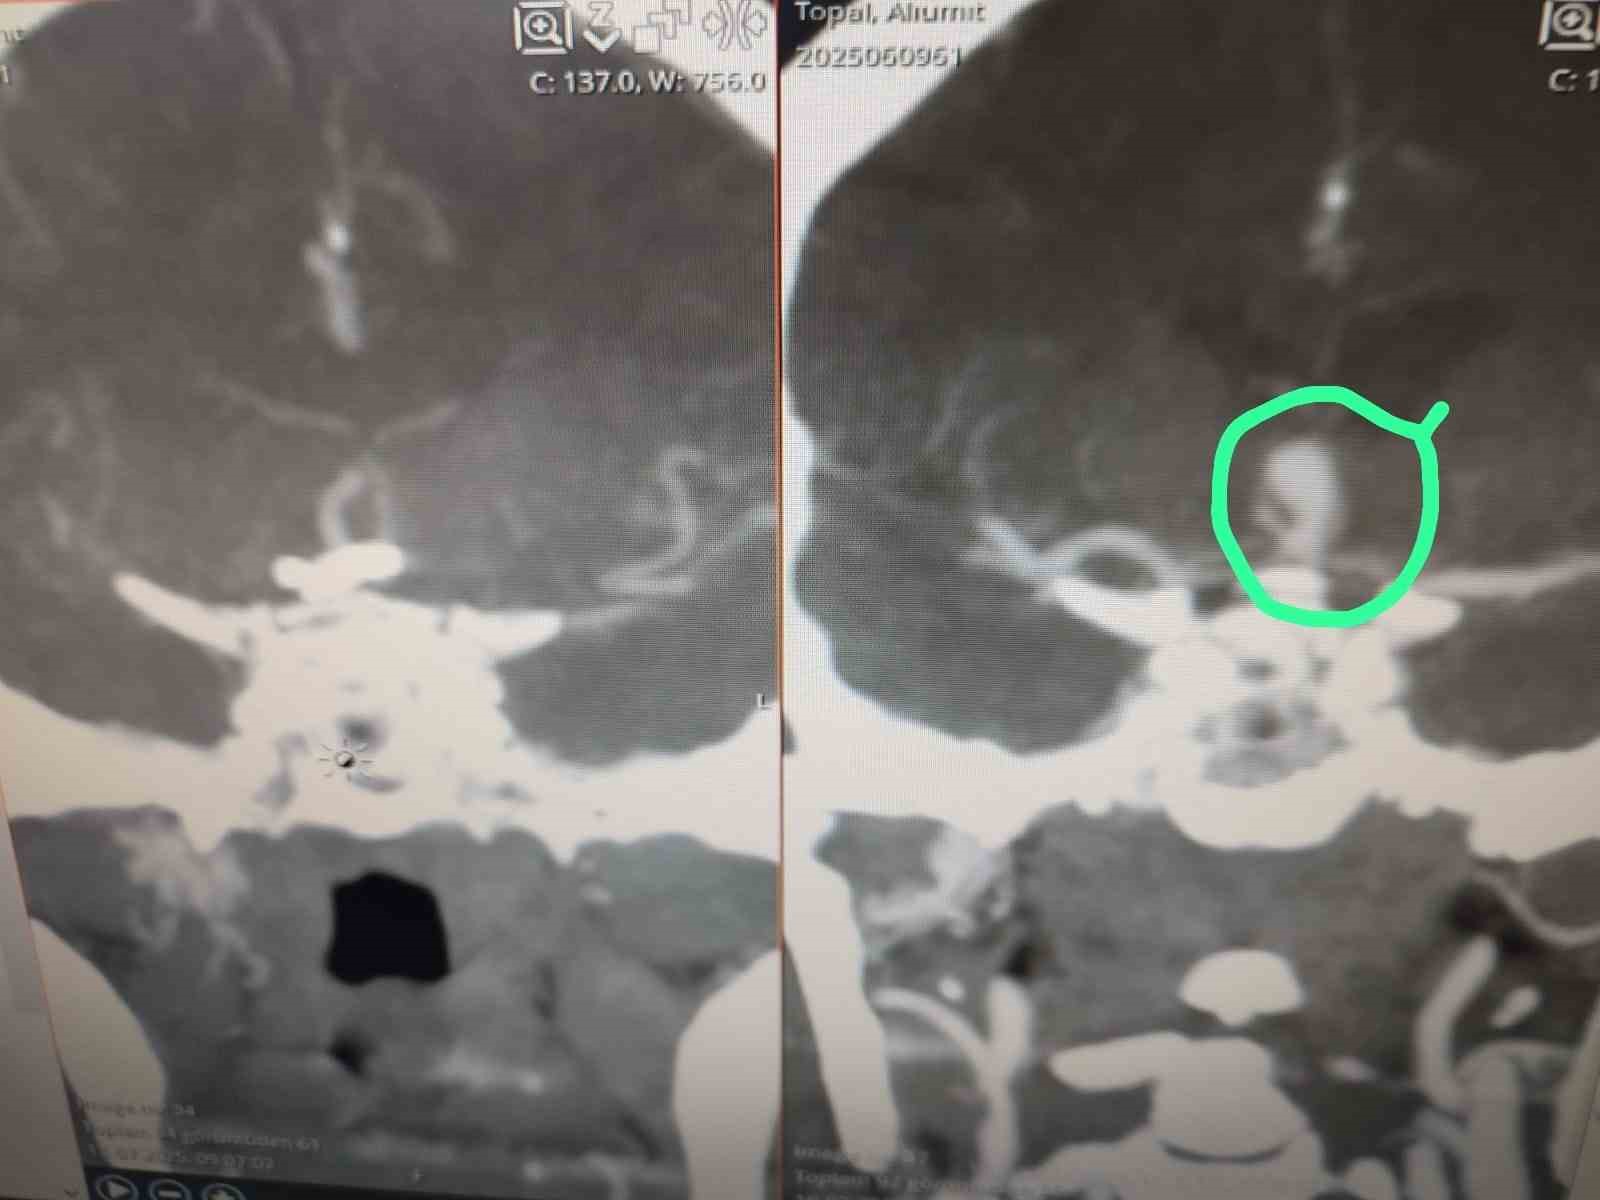

Antalya’nın Serik ilçesinde beyninde baloncuk (anevrizma) tespit edilen hasta, Serik Devlet Hastanesi’nde kaş üzerinden minimal bir kesi ile gerçekleştirilen operasyonla sağlığına kavuştu.

Beyninde anevrizma tespit edilen hasta, Serik Devlet Hastanesi’nde kaş üzerinden minimal bir kesi ile gerçekleştirilen operasyonla sağlığına kavuştu. Beyin ve sinir cerrahisi uzmanları Op. Dr. Ömer Elçik ve Op. Dr. Salim Tekir tarafından uygulanan yeni yöntem sayesinde hastanın ameliyat sonrası sürecinin hem daha konforlu geçtiği hem de estetik açıdan iz bırakmadığı bildirildi. Geleneksel beyin cerrahisinde kullanılan geniş kesiler yerine uygulanan modern teknik, özellikle yüz bölgesinde iz kalmasını istemeyen hastalar için önemli bir gelişme olarak değerlendiriliyor. Operasyonun ardından hasta kısa sürede taburcu edildi.